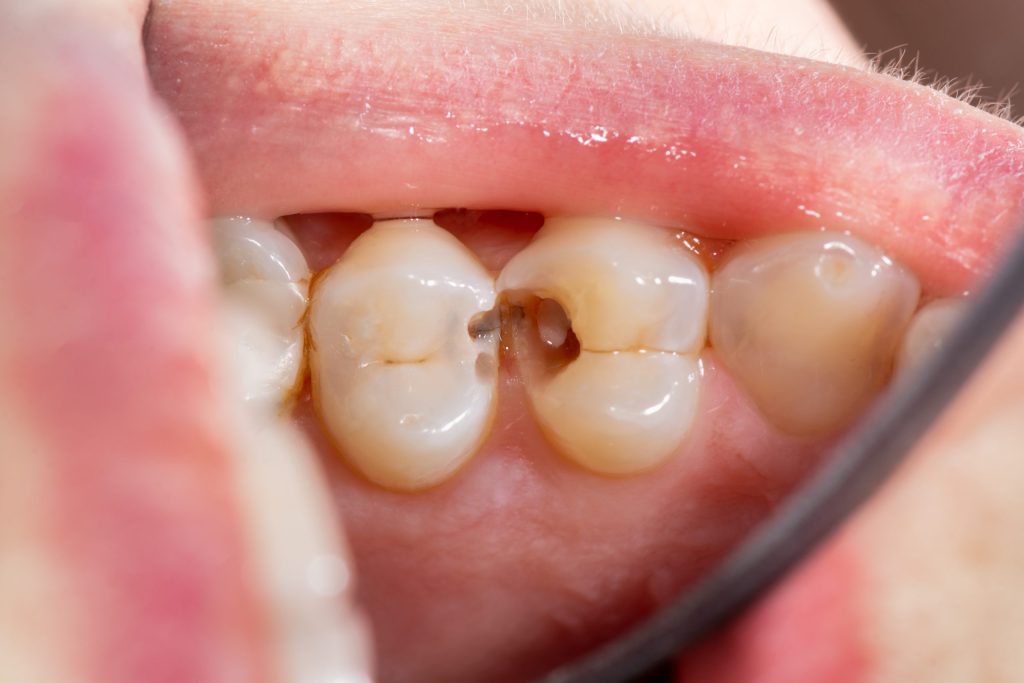

1. Presenza di carie dentale

La causa più frequente è la carie, un processo infettivo che distrugge progressivamente lo smalto e la dentina. Si ricorre all’otturazione quando la carie è in fase iniziale o intermedia, prima che raggiunga la polpa dentale (la parte più interna del dente, ricca di terminazioni nervose).

Sintomi tipici:

Alitosi persistente

Sensibilità a caldo, freddo o zuccheri

Dolore localizzato

Macchie scure o fori visibili sul dente